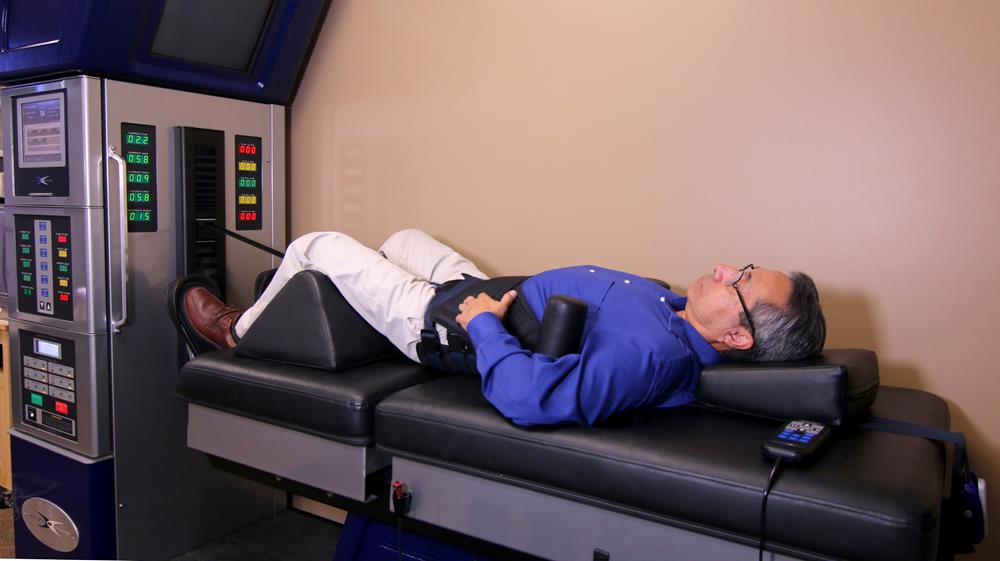

Spinal Decompression

Spinal decompression is a non-invasive mechanical procedure performed within our office to help alleviate back pain. It involves gently stretching the spine to take pressure off the spinal discs (the cushions that separate the vertebrae in the spine). By relieving this pressure, bulging discs can retract back into place which takes pressure off the nerves in the spine. By decompressing the spine, it permits water, oxygen and other fluids to work their way back into the discs allowing them to heal naturally. Spinal decompression is an excellent option for anyone with chronic back pain who wants to get back to living a pain-free life as quickly as possible.